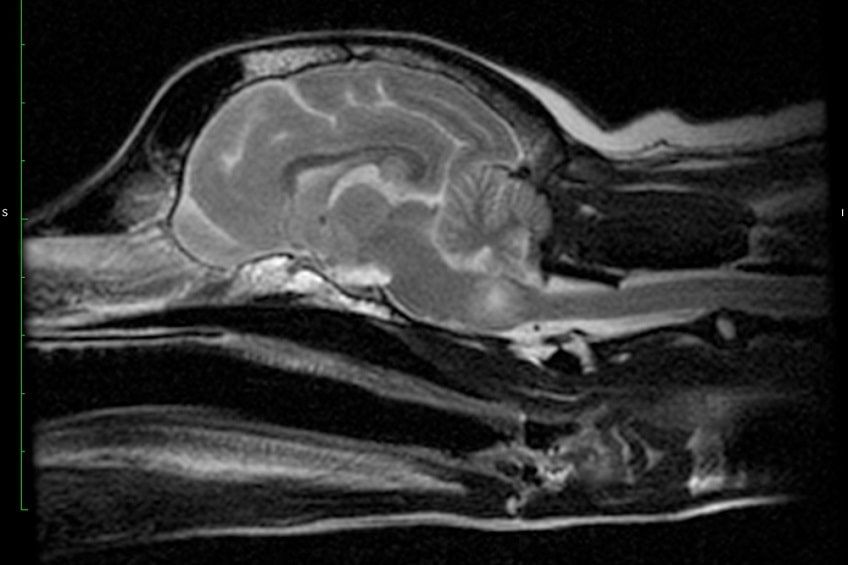

Po wstępnym ustaleniu przyczyny zaburzeń neurologicznych dalsza diagnostyka opiera się głównie na badaniach obrazowych. Ocenę budowy mózgu i rdzenia kręgowego umożliwia tomografia komputerowa lub rezonans magnetyczny. Takie badania są jednak drogie i trudno dostępne, dlatego częściej wykorzystuje się RTG i USG. W zależności od występujących objawów psu można także wykonać badanie płynu mózgowo-rdzeniowego lub EEG.